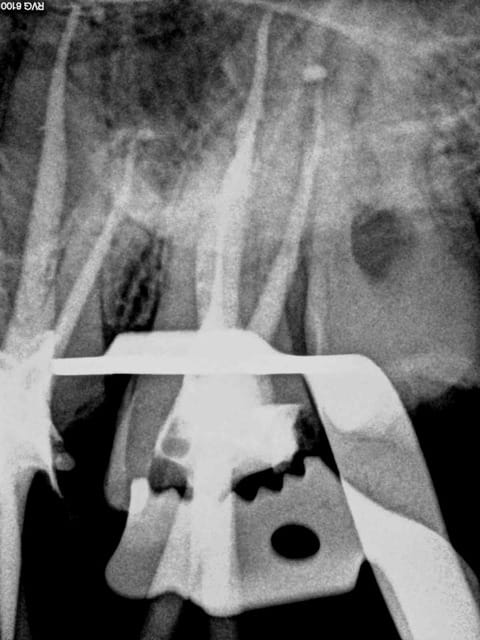

A 200 ° le plugger heater le ciment de scellement de cone tubuli seal prend fissa. Et pas de spray. ( logement fait avant l'obturation au largo puis la gutta thermocompactée de la longueur du tenon est virée au plugger heater , reste à passer un foret pivomatic). En un temps ca permet de raser les antérieures avant de faire l'endo, ca dégage le champ de vision et on centre mieux pour atteindre la pulpe meme rétractée.

Toute la finesse de la dentisterie francaise économe de tissus dentaires grace à une nomenclature à la pointe de la dentisterie! -))))